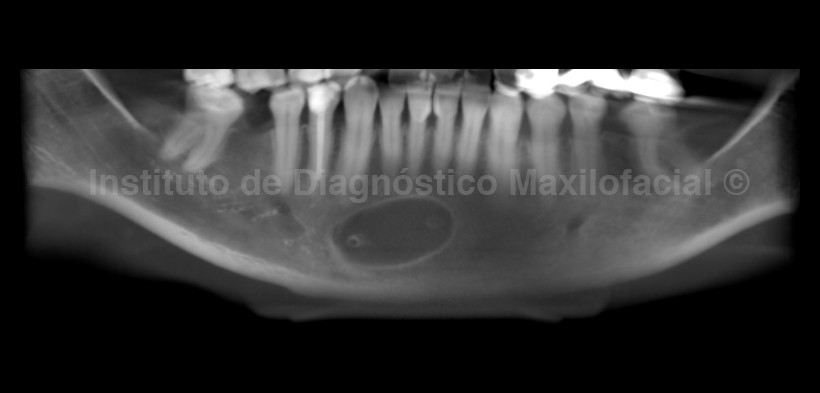

En la radiografía panorámica (Fig. 1) se observa una imagen radiolúcida de limites definidos y corticalizados proyectada en la zona sinfisiaria, en relación de cercanía con el periápice de las piezas 3.1, 4.1, 4.2, y 4.3 y con la basal mandibular, por otro lado se observan múltiples restauraciones coronales, la presencia de un puente protésico en el segundo cuadrante, la ausencia de multiples piezas dentarias y, como un hallazgo adicional, las calcificaciones a nivel de la cámara pulpar en las piezas posteriores de ambos maxilares.